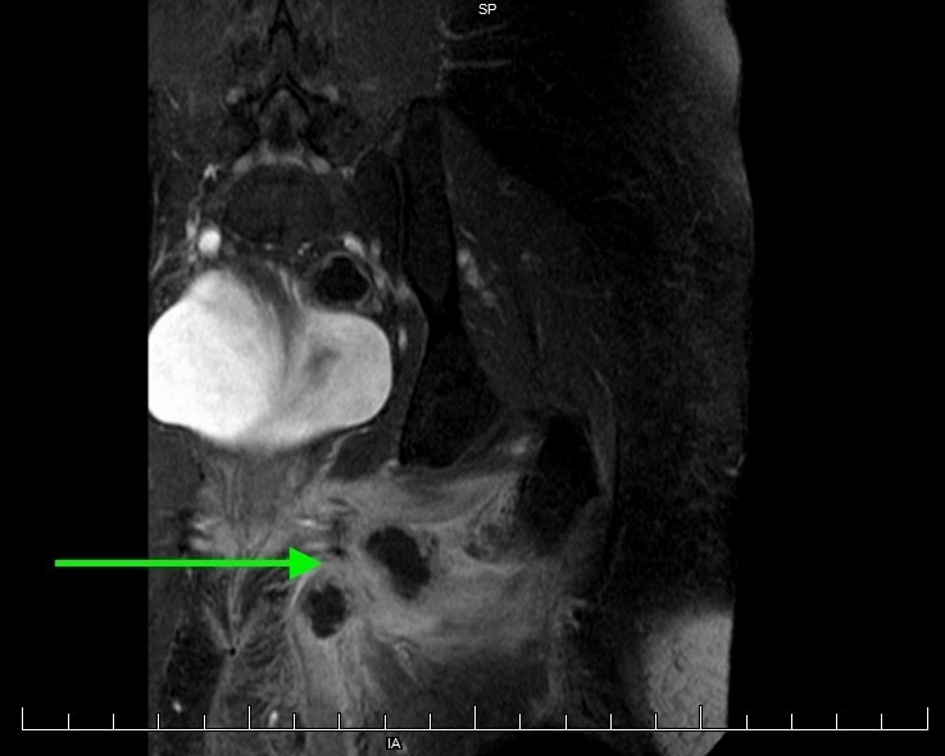

She presented to our institution with left groin and upper thigh cellulitis. On magnetic resonance imaging (MRI), she was found to have a multi-loculated abscess and myositis in the left groin involving the left adductor magnus, brevis, and longus muscles (Fig. 1). The patient was treated with broad-spectrum antibiotics, but continued to experience left groin and thigh pain with persistent abscess. She remained afebrile with negative blood and urine cultures. On ultrasound imaging, an echogenic structure in the left groin measuring 3.2 × 0.6 cm was thought to be consistent with residual transobturator mesh. A 3.0 × 3.4 × 2.7 cm abscess was also seen (Fig. 2). No mesh could be visualized on internal exam, but a pin point area of friable granulation tissue with purulent drainage was palpated on the left lateral vaginal wall, which was tender on exam. A firm mass was palpated in the left groin, consistent with the abscess seen on imaging.

![]() Click for large image | Figure 1. MRI of left groin abscess with associated inflammation. |